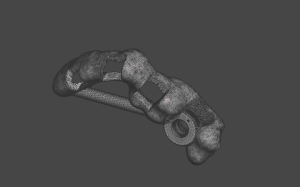

Fabricación de guía quirúrgica

Diseño y colocación de implantes / Fabricación de guía quirúrgica

Guia de recorte óseo

Guía de recorte óseo